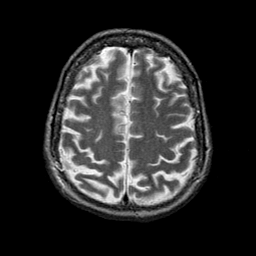

Alzheimer's disease: overlay -- Slice #19

[Home][Help][Clinical] Slice 19